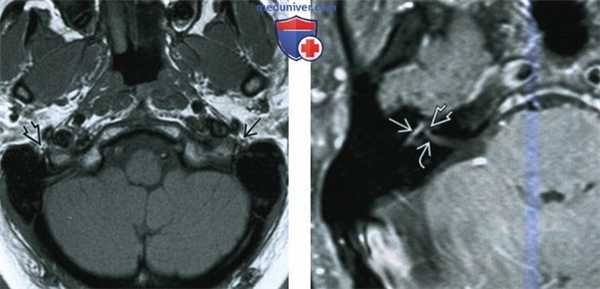

(Слева) МРТ, постконтрастное Т1-ВИ, режим подавления сигнала от жира, корональный срез: у пациента с правосторонним параличом Белла определяется выраженное асимметричное контрастирование сосцевидного сегмента правого ЧН VII по сравнению с минимальным контрастированием аналогичного участка ЧН VII слева.

(Справа) МРТ, постконтрастное Т-ВИ, режим подавления сигнала от жира, корональный срез: у этого же пациента определяется схожий характер контрастирования правого коленчатого ганглия по сравнению с левым. Это наблюдение можно объяснить тем, что коленчатый ганглий, наряду с задним коленом/верхним сосцевидным сегментом лицевого нерва могут контрастроваться и в норме.

(Слева) МРТ, Т1-ВИ, аксиальный срез: у пациента с левосторонним параличом Белла в области шилососцевидного отверстия определяется увеличение левого лицевого нерва по сравнению с правым. Набухание поврежденного левого лицевого нерва возникает в том случае, если он не ограничивается стенками канала лицевого нерва височной кости.

(Справа) МРТ, постконтрастное Т1-ВИ, режим подавления сигнала от жира, аксиальный срез: у пациента с правосторонним параличом Белла определяются типичные для данной патологии признаки: контрастирование барабанного и лабиринтного сегментов лицевого нерва. Обратите внимание на наличие малозаметного признака «хохолка» в области дна ВСП.

(Слева) При корональной МРТ Т1 ВИ С+ FS у пациента с правосторонним параличом Белла определяется асимметричное интенсивное контрастирование сосцевидною сегмента ЧН VII справа по сравнению с минимальным контрастированием слева.

(Справа) При корональной MPT Т1 ВИ С+ FS у этою же пациента определяется аналогичное контрастное усиление правою коленчатою ганглия по сравнению с левым. Это можно объяснить тем фактом, что коленчатый ганглий, как и заднее колено/верхний сосцевидный сегмент лицевою нерва могут в норме накапливать контраст.

(Слева) При аксиальной МРТ Т1 ВИ у пациента с параличом Белла левый лицевой нерв в шилососцевидном отверстии больше правого. Пораженный левый лицевой нерв отекает, где он не ограничен костным интратемпоральным каналом.

(Справа) При аксиальной МРТ Т1 ВИ С+ FS у пациента с правосторонним параличом Белла определяется типичное контрастное усиление барабанного и лабиринтного сегментов лицевого нерва. Обратите внимание на менее выраженный симптом «хохолка» в области дна ВСК.